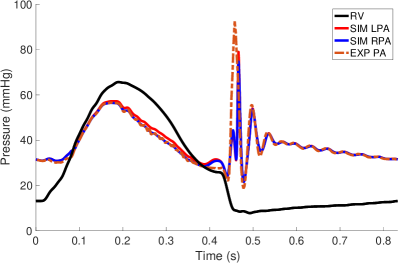

Pressure and flow waveforms from the second cycle in the simulation and the experiment are shown in Figure 7. During systole, the pressures were prescribed. During valve closure, the pressures showed an oscillation as determined by the interaction of the prescribed pressure and resistance (Equation 14). The experimental pulmonary artery pressure had a similar oscillation, but not with precisely the same magnitude or frequency. The RV flow rate closely matched that of the experimental flow. The RPA flow was somewhat greater than the experimental RPA flow, and the LPA flow was somewhat less than the experimental LPA flow. The total experimental flow was not precisely conserved, which is expected given pointwise uncertainty in the 4D flow MRI velocity measurements of 4.7 cm/s, uncertainty in gating of the cardiac cycles and variation from cycle to cycle. The total experimental inflow minus total outflow was up to 27.0 ml/s, which is nearly all experimental uncertainty, as the vessel maintains approximately constant volume. Therefore, it was not possible to simultaneously match all three experimental flow rates. All three simulation flow rates showed a substantial oscillation at the beginning of diastole. Similar oscillations in the experimental flow rates almost surely occurred but could not be captured due to the time resolution of the 4D flow MRI data. We estimated the stroke volume to be 46.11 ml and cardiac output to be 3.32 L/min. Using the maximum flow rate of ml/s and diameter of the valve, 2 cm, as the length scale, we estimated the peak Reynolds number of the flow as

| (19) |

where is the valve orifice area. The Reynolds number is much greater than one and indicates that the flow was in a physically unstable regime.